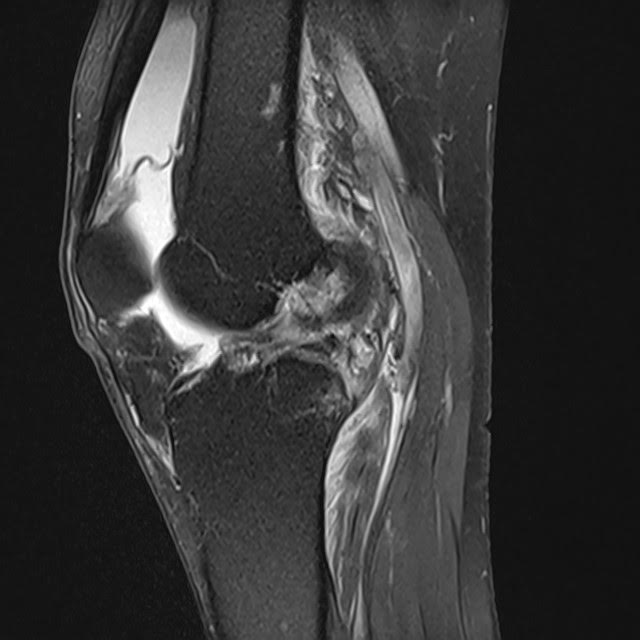

križne vezi | Foto: UKC Ljubljana Foto: UKC Ljubljana

"Pretrganje vezi pomeni, da se zaradi prevelike obremenitve pri športu strga sprednja križna vez, ki je ena od vezi, ki povezujejo stegnenico in golenico v kolenskem sklepu. Pogovorno imenovanje križnih vezi se nanaša praviloma na eno, najpogosteje poškodovano: sprednjo križno vez. Posledica popolnega pretrganja te vezi je določena stopnja nestabilnosti kolenskega sklepa, odvisno od tega, kako močne in koordinirane so mišice noge," je v izjavi za UKV pojasnil Marko Macura, travmatolog in dolgoletni zdravnik slovenske košarkarske reprezentance.

Je pri pretrganih križnih vezeh vedno potrebna operacija poškodovancev? "Ne vedno. Odločamo se glede na stopnjo poškodbe in morebitne pridružene poškodbe kosti, hrustanca, meniskusov, drugih vezi ter glede na pričakovano stopnjo aktivnosti oz. funkcionalne zahteve. Po podatkih švedskega registra poškodb kolenskih vezi se kirurgi ob prvem srečanju s pacientom v polovici primerov odločijo za operacijo, v polovici pa za fizioterapijo."